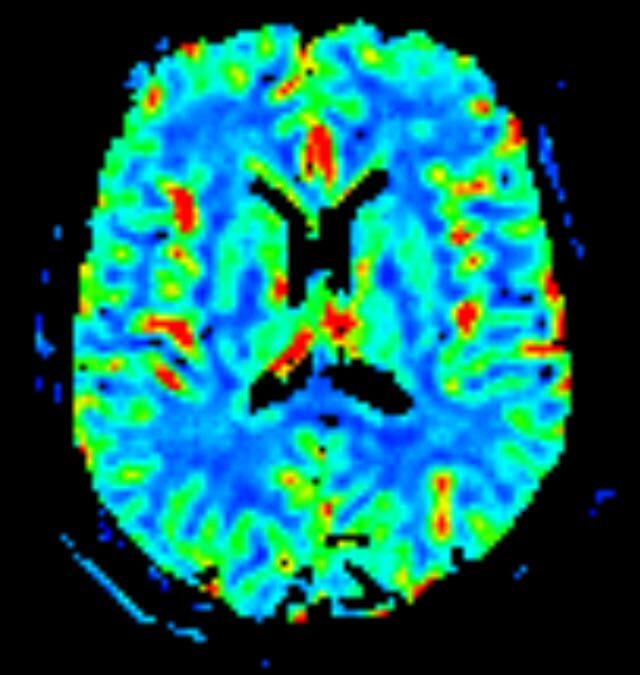

- Diffusionswichtung

- Perfusionswichtung

- Suszeptibilitätswichtung

- MR-Spektroskopie

Diese Verfahren werden bei verschiedenen Fragestellungen in verschiedenen Körperregionen in die Messprotokolle sinnvoll eingefügt. Teilweise können dadurch Differenzierungenverschiedener krankhafter Prozesse verbessert werden.